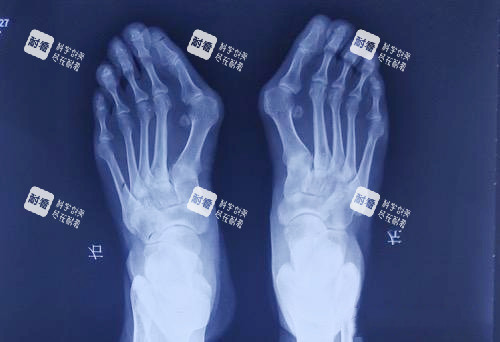

2025年8月,我揣着攒了半年的私房钱,战战兢兢地去了北京圣嘉新。苏医生拿着我的X光片,指着电脑上3D模拟的脚部模型说:“你这属于中度拇外翻,大脚趾偏斜25度,二三脚趾也被挤得变形了,得做双侧矫正,费用大概2.4万。”